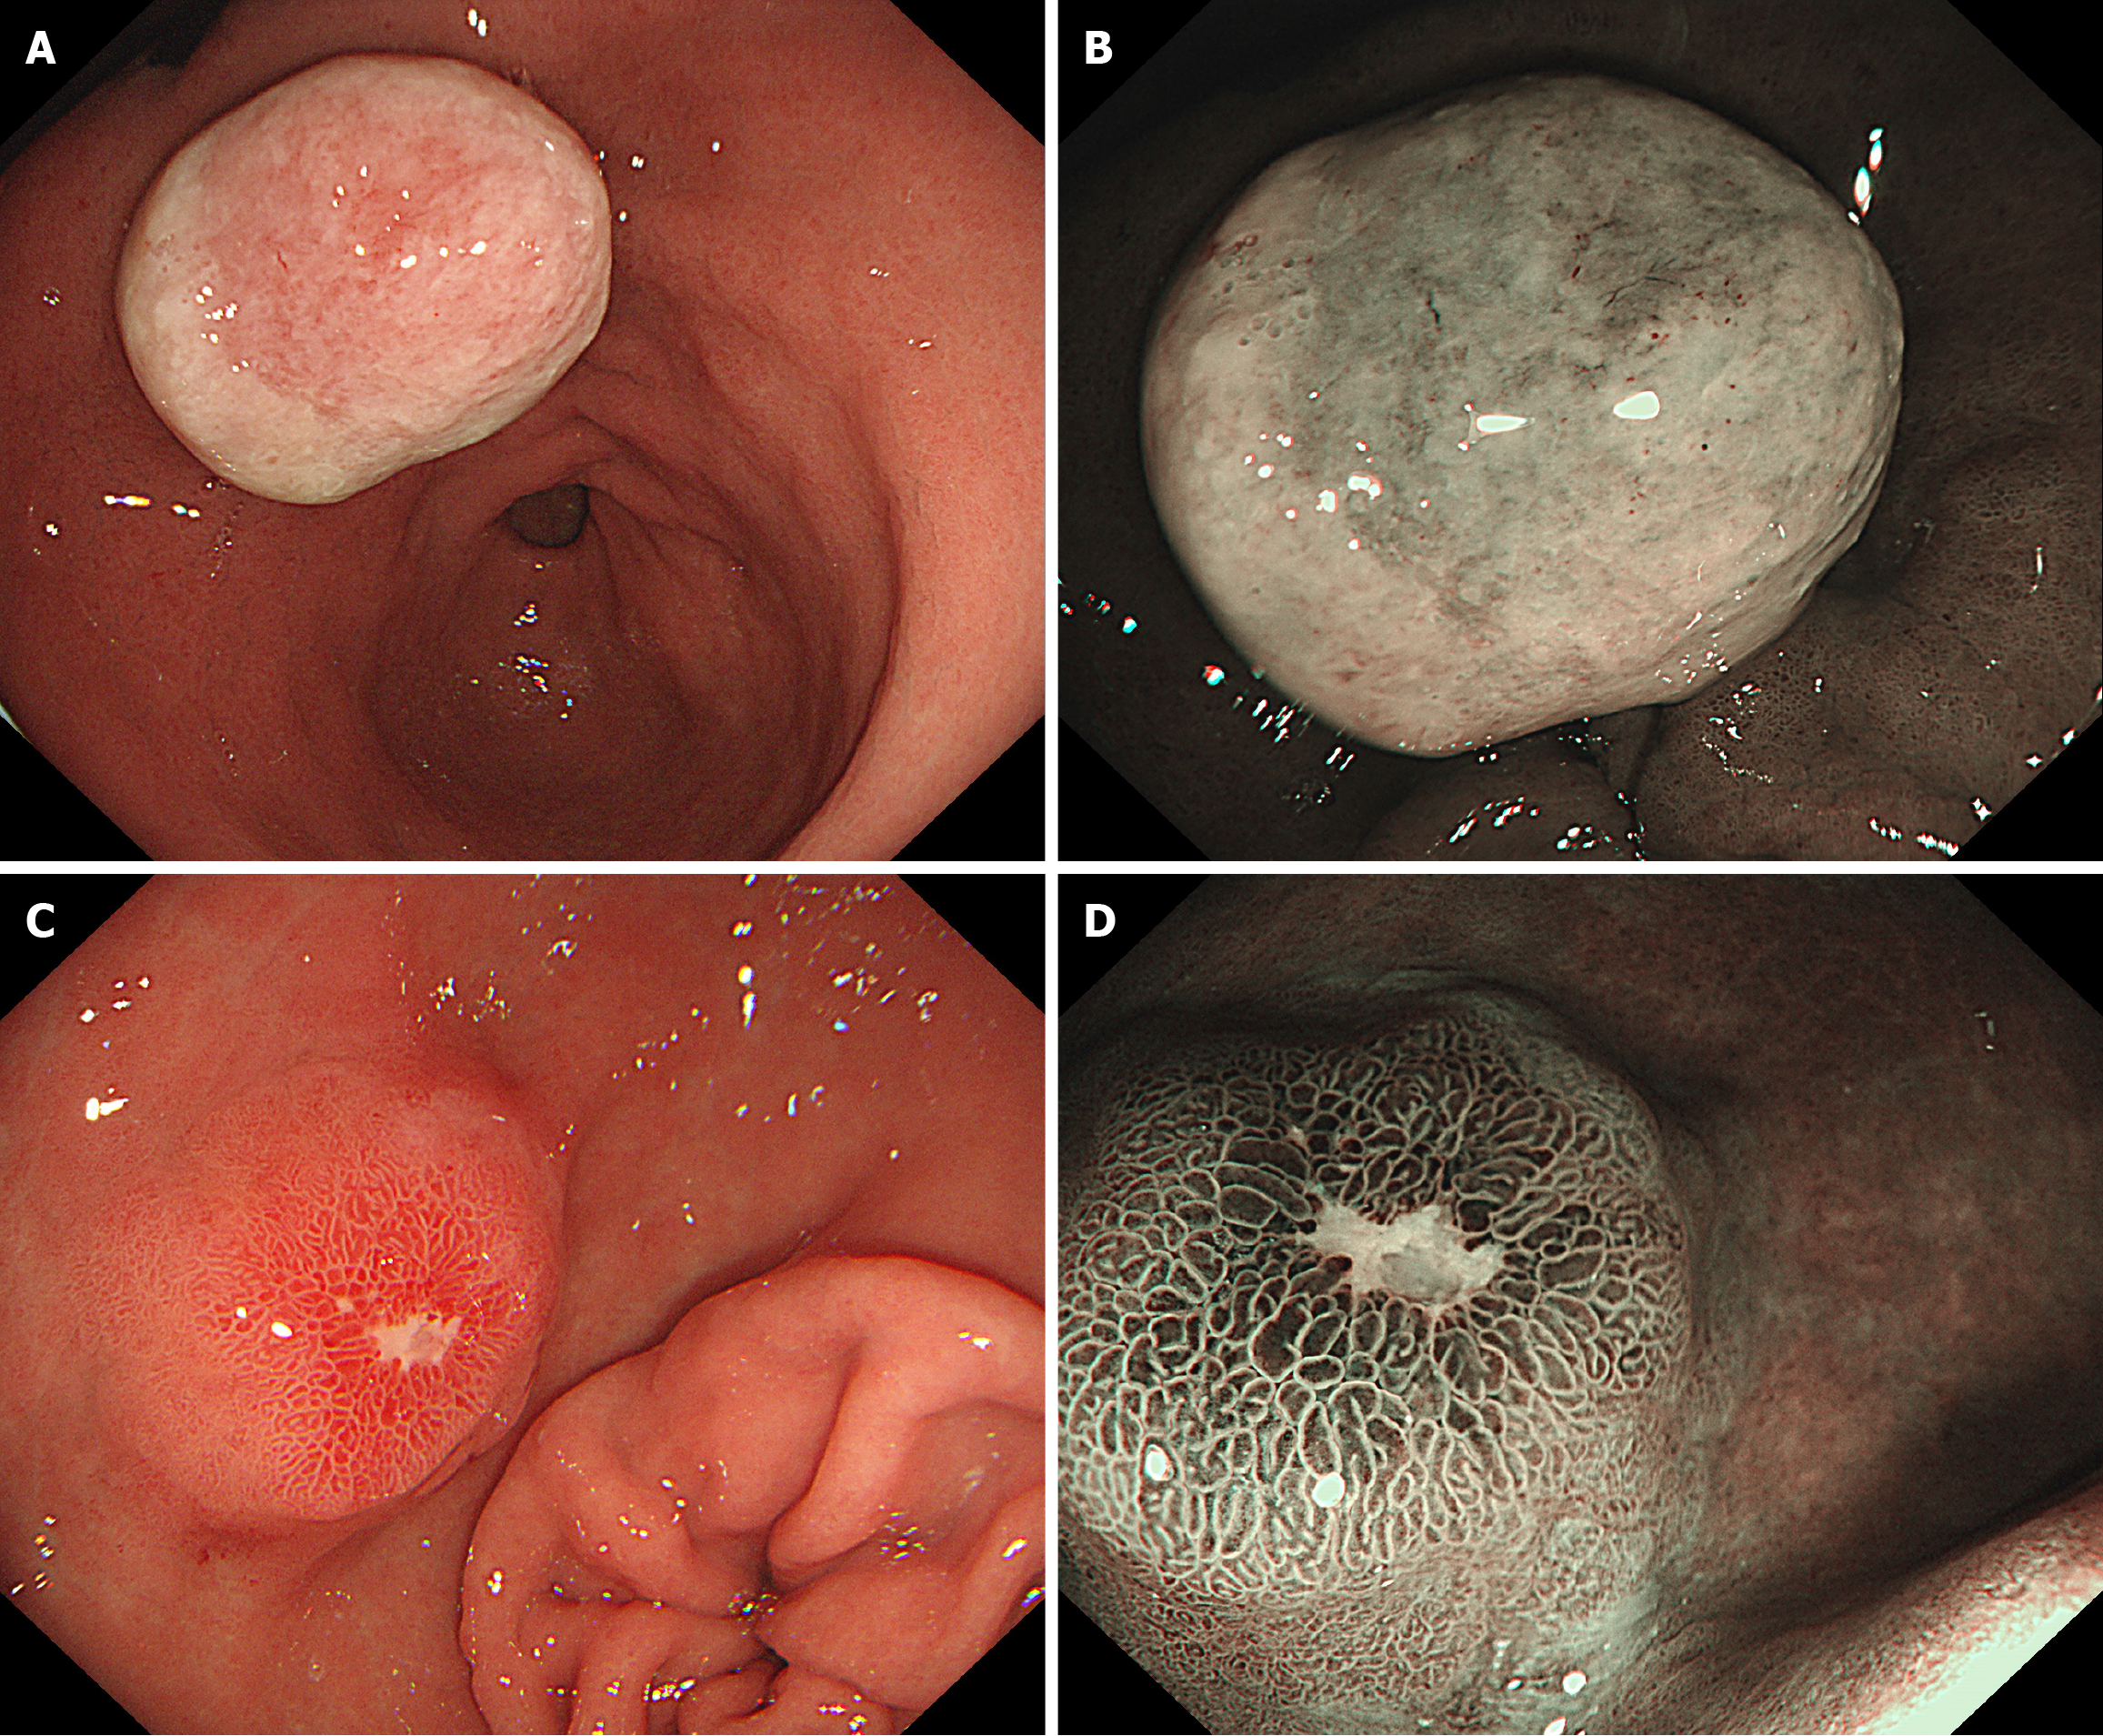

Figure 2 Comparison of proton pump inhibitors before and after treatment.

A: White light before proton pump inhibitors (PPIs) treatment: A 2 cm protrusion is seen in the lesser curvature of the gastric antrum, with surface coating attached; B: magnifying endoscopy with narrow-band imaging (ME-NBI) before PPIs treatment: Ulcer tissue attachment; C: White light after PPIs treatment: The bulge has shrunk compared to before, the surface of the lesion exhibited congestion, edema, erosion, hard texture upon palpation, and poor mobility; D: ME-NBI after PPIs treatment: Regular vascular pattern, normal pit pattern.